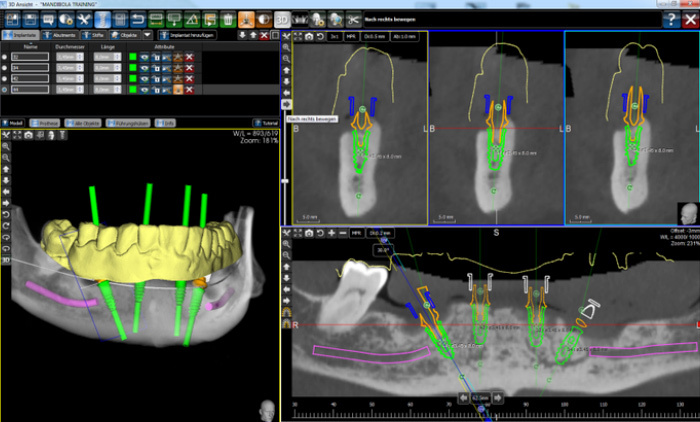

Sobald alle finanziellen Fragen geklärt sind, beginnen wir in unserer Praxis in Stuttgart mit der 3D-Diagnostik. Dazu wird ein sogenanntes DVT, eine digitale Volumentomographie, erstellt. Diese 3D-Aufnahme gibt uns die Möglichkeit, Ihren Kiefer präzise auszumessen und die genaue Implantatposition vorher mittels spezieller Software festzulegen.

Als Nächstes erstellen wir einen digitalen Abdruck Ihrer Zähne mit einem Intraoralscanner. Die Daten werden genutzt, um eine Schablone herzustellen, die exakt auf Ihren Kiefer angepasst ist. Mithilfe dieser Schablone wird die Implantation durchgeführt. Darin enthaltene Führungshülsen erlauben es, das Implantat so zu setzen, wie wir es zuvor in der Software geplant haben. So stellen wir sicher, dass die Zahnimplantate die richtige Ausrichtung haben und genau so im Kiefer sitzen, wie es vorher Ihr natürlicher Zahn tat.

Die navigierte Implantation

Die Schablone enthält präzise Führungshülsen, die es uns erlauben, das Implantat exakt so zu setzen, wie wir es zuvor in der Software geplant haben. So stellen wir sicher, dass das Zahnimplantat die richtige Ausrichtung hat und genau so im Kiefer sitzt, wie es vorher Ihr natürlicher Zahn tat. Die Schablone macht die Behandlung sowohl für unsere Patienten und Patientinnen als auch für den Implantologen bzw. die Implantologin deutlich entspannter und gleichzeitig schneller. Dank der richtigen Vorbereitung dauert es nur etwa zehn Minuten, ein Implantat präzise einzusetzen.Eine navigierte Implantation kommt ohne Skalpell und Naht aus. Dementsprechend benötigen Sie bei der Zahnimplantation in Stuttgart auch keine Vollnarkose. Eine örtliche Betäubung ist in der Regel völlig ausreichend. Die Stelle, an der das Implantat eingesetzt wird, verheilt dabei in der Regel innerhalb von zwei bis drei Tagen.